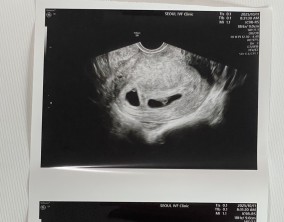

눈물로 실감한 아홉 번째 주

이경훈 원장님은 검사를 통해 나온 수치와 결과에 대해 자세히 설명해 주시고, 상황에 맞는 여러 방법을 함께 제시해 주셔서 큰 신뢰와 감사함을 느꼈습니다. 불안을 혼자 짊어지…